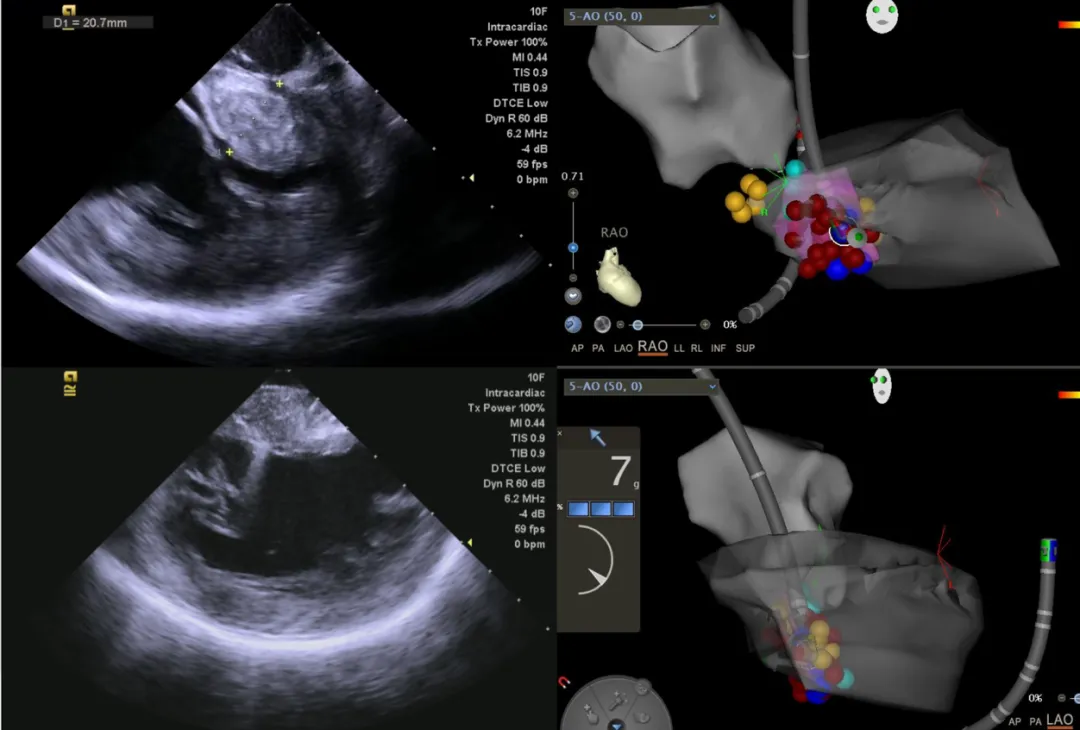

经皮心内膜室间隔射频消融术通过心腔内超声和CARTO三维标测系统定位并标记室间隔梗阻的关键区域(SAM区,紫色范围),避开标记好的房室传导束(黄点)对SAM区充分进行射频消融,从而减轻流出道梗阻,缓解患者症状。

经过详细的术前讨论和准备,4月25日,该院心病科介入团队成功为冯女士开展手术治疗。手术通过穿刺股静脉和股动脉的微创方式进行,整个过程持续约2小时,消融过程中可见室间隔水肿带出现,二尖瓣收缩期前叶前移(SAM)现象明显减轻。

消融结束后复测左室有创压力示跨流出道压力阶差为10mmHg(术前为58mmHg),床旁超声测左室流出道压差为18mmHg,均较前下降大于50%,成功减轻梗阻。术后冯女士恢复良好,次日即可下地活动,复查心脏彩超示左室流出道梗阻明显改善。